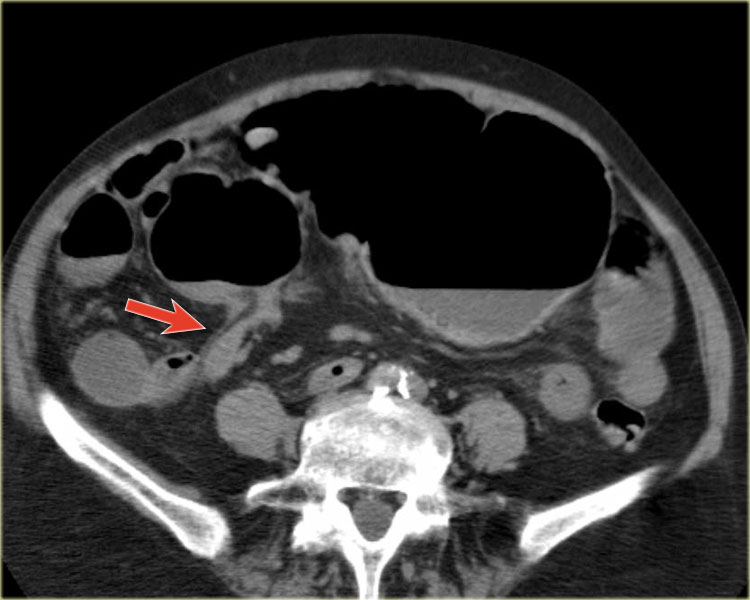

Bên trái là các hình ảnh CT bổ sung của cùng bệnh nhân nêu trên.

Đầu tiên, chúng ta thấy đại tràng xuống xẹp và đại tràng lên không giãn, do đó đây không thể là xoắn đại tràng sigma.

Thứ hai, chúng ta thấy một cấu trúc hình mỏ chim ở góc phần tư dưới bên phải, đây là vị trí xoắn của ruột.

Ở góc phần tư dưới bên trái, chúng ta thấy manh tràng giãn.

Tái tạo ảnh mặt phẳng coronal có thể rất hữu ích trong việc thể hiện toàn cảnh tổn thương.

Bên trái, chúng ta thấy đại tràng lên và đại tràng xuống không giãn (mũi tên thẳng) và điểm chuyển tiếp của xoắn (mũi tên cong).